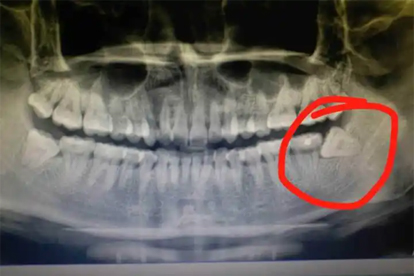

拔智齿后通常需要3-7天才能进行轻度运动,具体恢复时间因个人体质和手术情况而异。剧烈运动建议在7-14天后进行,过早运动可能导致伤口出血或感染,影响愈合。

拔智齿后3天内是伤口恢复的关键期,此时应避免任何形式的运动,主要以静养为主。3-7天内可以适当进行散步等轻度活动,但需避免头部剧烈晃动或弯腰等可能增加口腔压力的动作。7天后,若伤口无明显疼痛或出血症状,可以逐步恢复轻度有氧运动,如慢跑或瑜伽。剧烈运动如篮球、足球等,建议在14天后进行,以确保伤口完全愈合。运动时需注意及时补充水分,避免过度疲劳,并密切关注口腔状况,如出现异常应立即停止运动并咨询医生。